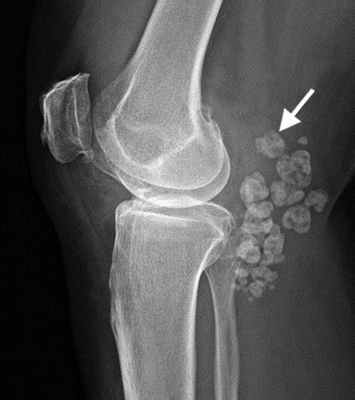

Рентгенография суставов - в области правого коленного сустава выявляются множественные, свободно располагающиеся в его полости, супрапателлярной сумке овальной и округлой формы образования (рис. 1). Рентгенснимки были проконсультированы с профессором И.В. Красицким. Высказано мнение о первичном остеохондроматозе. Больному предложено артроскопическое вмешательство, от которого он воздержался.

Однако рентгенографическая картина позволила кардинальным кардинальным образом изменить диагноз в пользу первичного синовиального остеохондроматоза правого коленного сустава. Данное профессором И.В. Красицким, на основании рентгенснимка, заключение об остеохондроматозе в наибольшей степени соответствовало именно данной клинической картине.

Рис. 1. Рентгенография коленного сустава в прямой и боковой проекции при остеохондроматозе больного З., 52 лет.